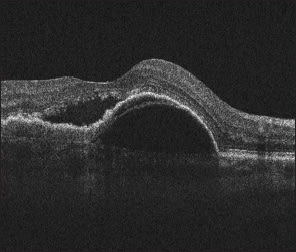

3. Chronic CSR: FAF vs. FA

Most Optimal Technique

Advantages: Shows classic gutter appearance for CSCR; fully captures RPE disruption.

Limitations: Does not show active source of leakage or “hot spot”; does not show extent of SRF; uses blue light.

Alternative Technique

Advantages: Technique is appropriate for imaging both acute and chronic CSR.

Limitations: Invasive; adverse reaction to dye.